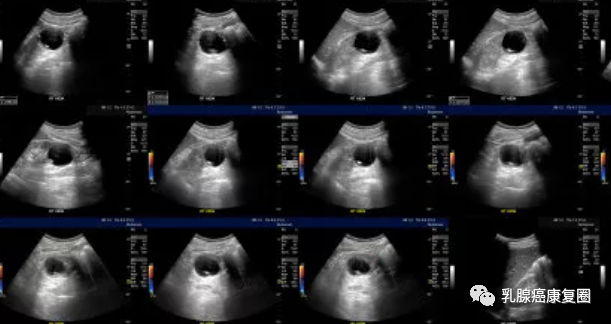

囊肿是最常被诊断出的乳房肿块,多见于35~50岁的女性。这些良性的、充满液体的囊泡可能从堵塞的乳管中发展而来。它们通常摸起来圆圆的、有点儿软,就像一个装水的小气球,但也可能会非常坚硬。乳腺囊肿是哺乳期女性出现的一种充满乳汁的囊肿。囊肿可能单个出现,也可能数量众多、间隔开来或者积聚在一起,小到肉眼无法观察,大到超过10厘米。它们通?;崴孀拍愕脑戮芷诜锤?,在月经到来时变得更大、更软,然后在几天之后恢复原状。超声检查可以轻而易举地识别出它们。一项大型研究发现,65.1%的绝经前期和39.4%的绝经后女性都有囊肿,而且其中半数女性的双侧乳房都有。研究已经证实使用激素替代疗法的女性在绝经前期患上囊肿的风险为66%,这不奇怪,因为囊肿对激素敏感。